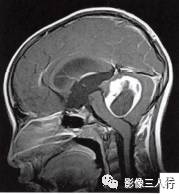

(二)影像所见

头颅MRI扫描示:小脑上蚓部见团块状异常信号影,边缘清楚,大小约4.5cm×3.5cm×3.7cm,T1WI(图B)等信号,中心可见更低信号,T2WI(图A)呈髙信号,水抑制(图C) 等信号,中心呈更低信号,周边可见轻度高信号水肿区。增强后(图D〜F)病灶可见明显环形强化,壁较厚,内壁欠光滑,邻近小脑及第四脑室受压,第三脑室、双侧脑室扩张积水。

诊断:小脑上蚓部占位,考虑肿瘤性病变,以毛细胞型星形细胞瘤可能性大。